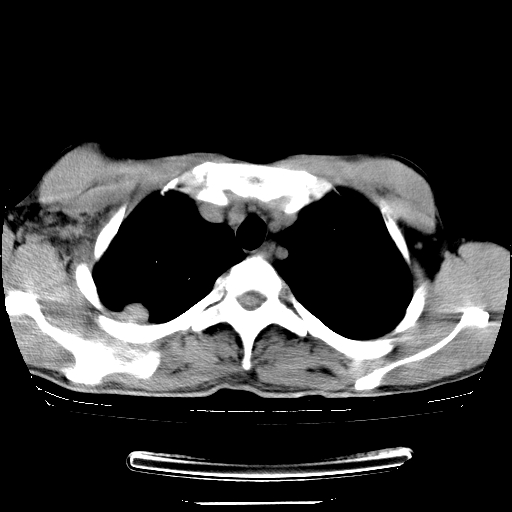

以下是引用dyqct在2008-4-29 8:43:00的发言:[br][br] 支持右侧胸腔包裹性积血。闭式引流管是不是插的太深了?

以下是引用zjzjr在2008-4-29 14:11:00的发言:[br]支持右侧胸腔包裹性积血。闭式引流管是不是插的太深了?胸腔引流,引流管快进入纵隔了.